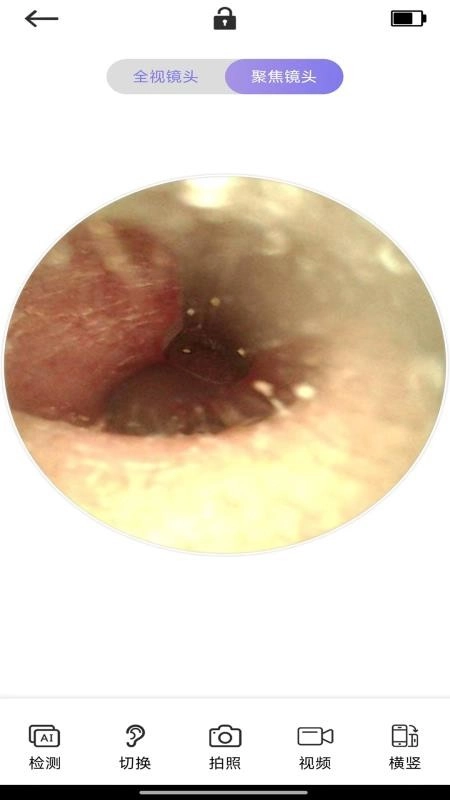

3、高清镜头

这段采耳镜头清晰度极高,还支持全视镜头与聚焦镜头两种拍摄模式,让你可以清晰查看细节。

这款应用配备强大的采耳镜头拍摄功能,能实时拍摄并监控采耳过程中的画面,让操作更加便捷。

2、镜头拍摄